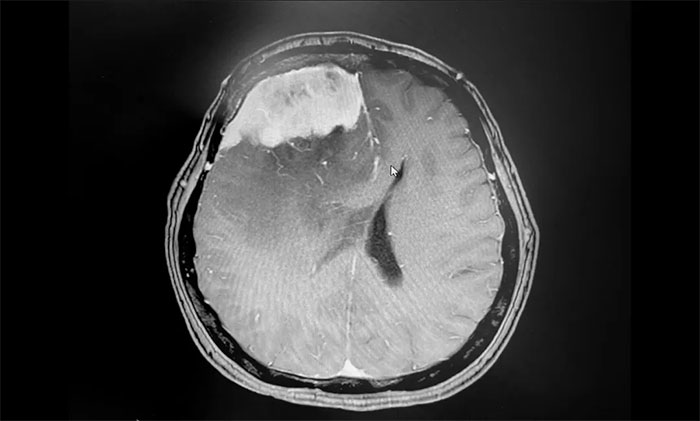

▲ 術(shù)后影像,腫瘤已切除

手術(shù)順利完成后,患者生命體征平穩(wěn),安返監(jiān)護(hù)病房。留取病理標(biāo)本送檢,確定為腦膜上皮型腦膜瘤(WHO I級(jí)),為良性腫瘤。